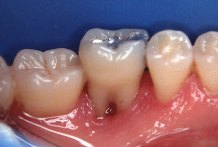

La

periodontitis, que normalmente se denomina "piorrea" (en griego "flujo de

pus"), incluye la inflamaci�n cr�nica y destrucci�n del hueso que soporta los

dientes. Tambi�n, las fibras gingivales y el ligamento periodontal son destruidos y el

borde de las enc�as se desprende de los dientes, formando lo que se llama una bolsa

periodontal en la cual puede aparecer pus. La bolsa periodontal se agranda si el hueso es

destruido m�s severamente y, en consecuencia, los dientes "se aflojan". Al

avanzar la enfermedad los dientes se pueden mover a�n m�s y es frecuente que se forme un

absceso e incluso que se caigan.